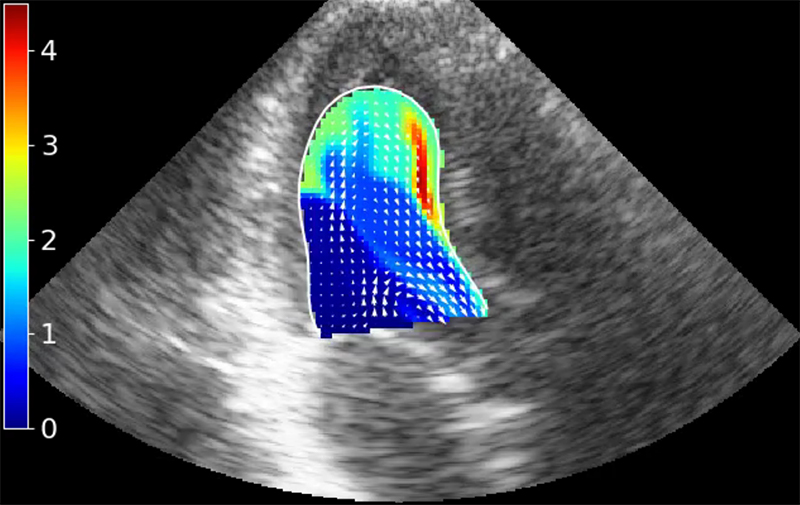

Veocor has developed the first cloud-based tool to diagnose the risk of cardiac thrombus formation and associated stroke. Veocor’s AI-powered technology quickly analyzes standard ultrasound images to provide a measure of blood flow in the left ventricle and identify regions at risk of thrombus formation. No additional hardware or training is required: cardiologists will be able to risk-stratify patients and identify who would benefit from anticoagulation.